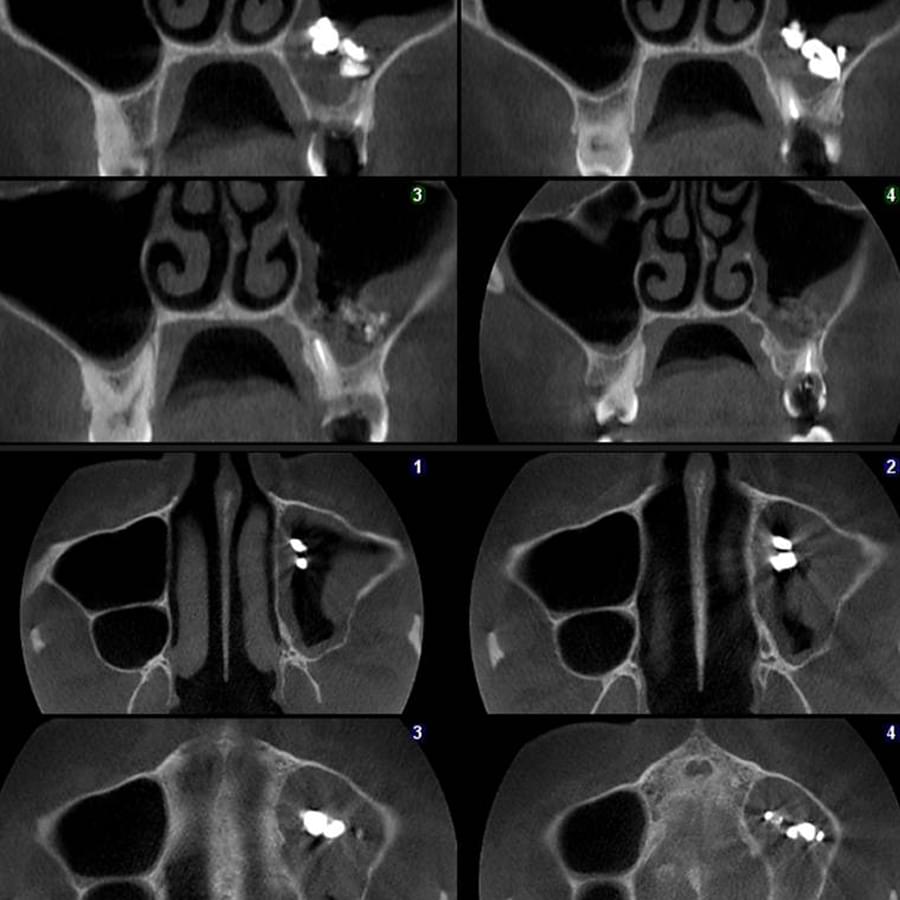

Мережа діагностичних центрів "МАЙРЕЙ ЛАБ" забезпечує точну та надійну діагностику

щелепно-лицевої ділянки з мінімальним ризиком для пацієнтів.

Ми використовуємо найсучасніше обладнання відомого виробника PLANMECA, що дозволяє отримувати високоякісні зображення за короткий час. Крім того, ми маємо власний сервер, на якому створюємо окрему скриньку для кожного лікаря, що забезпечує максимальну зручність та ефективність роботи.